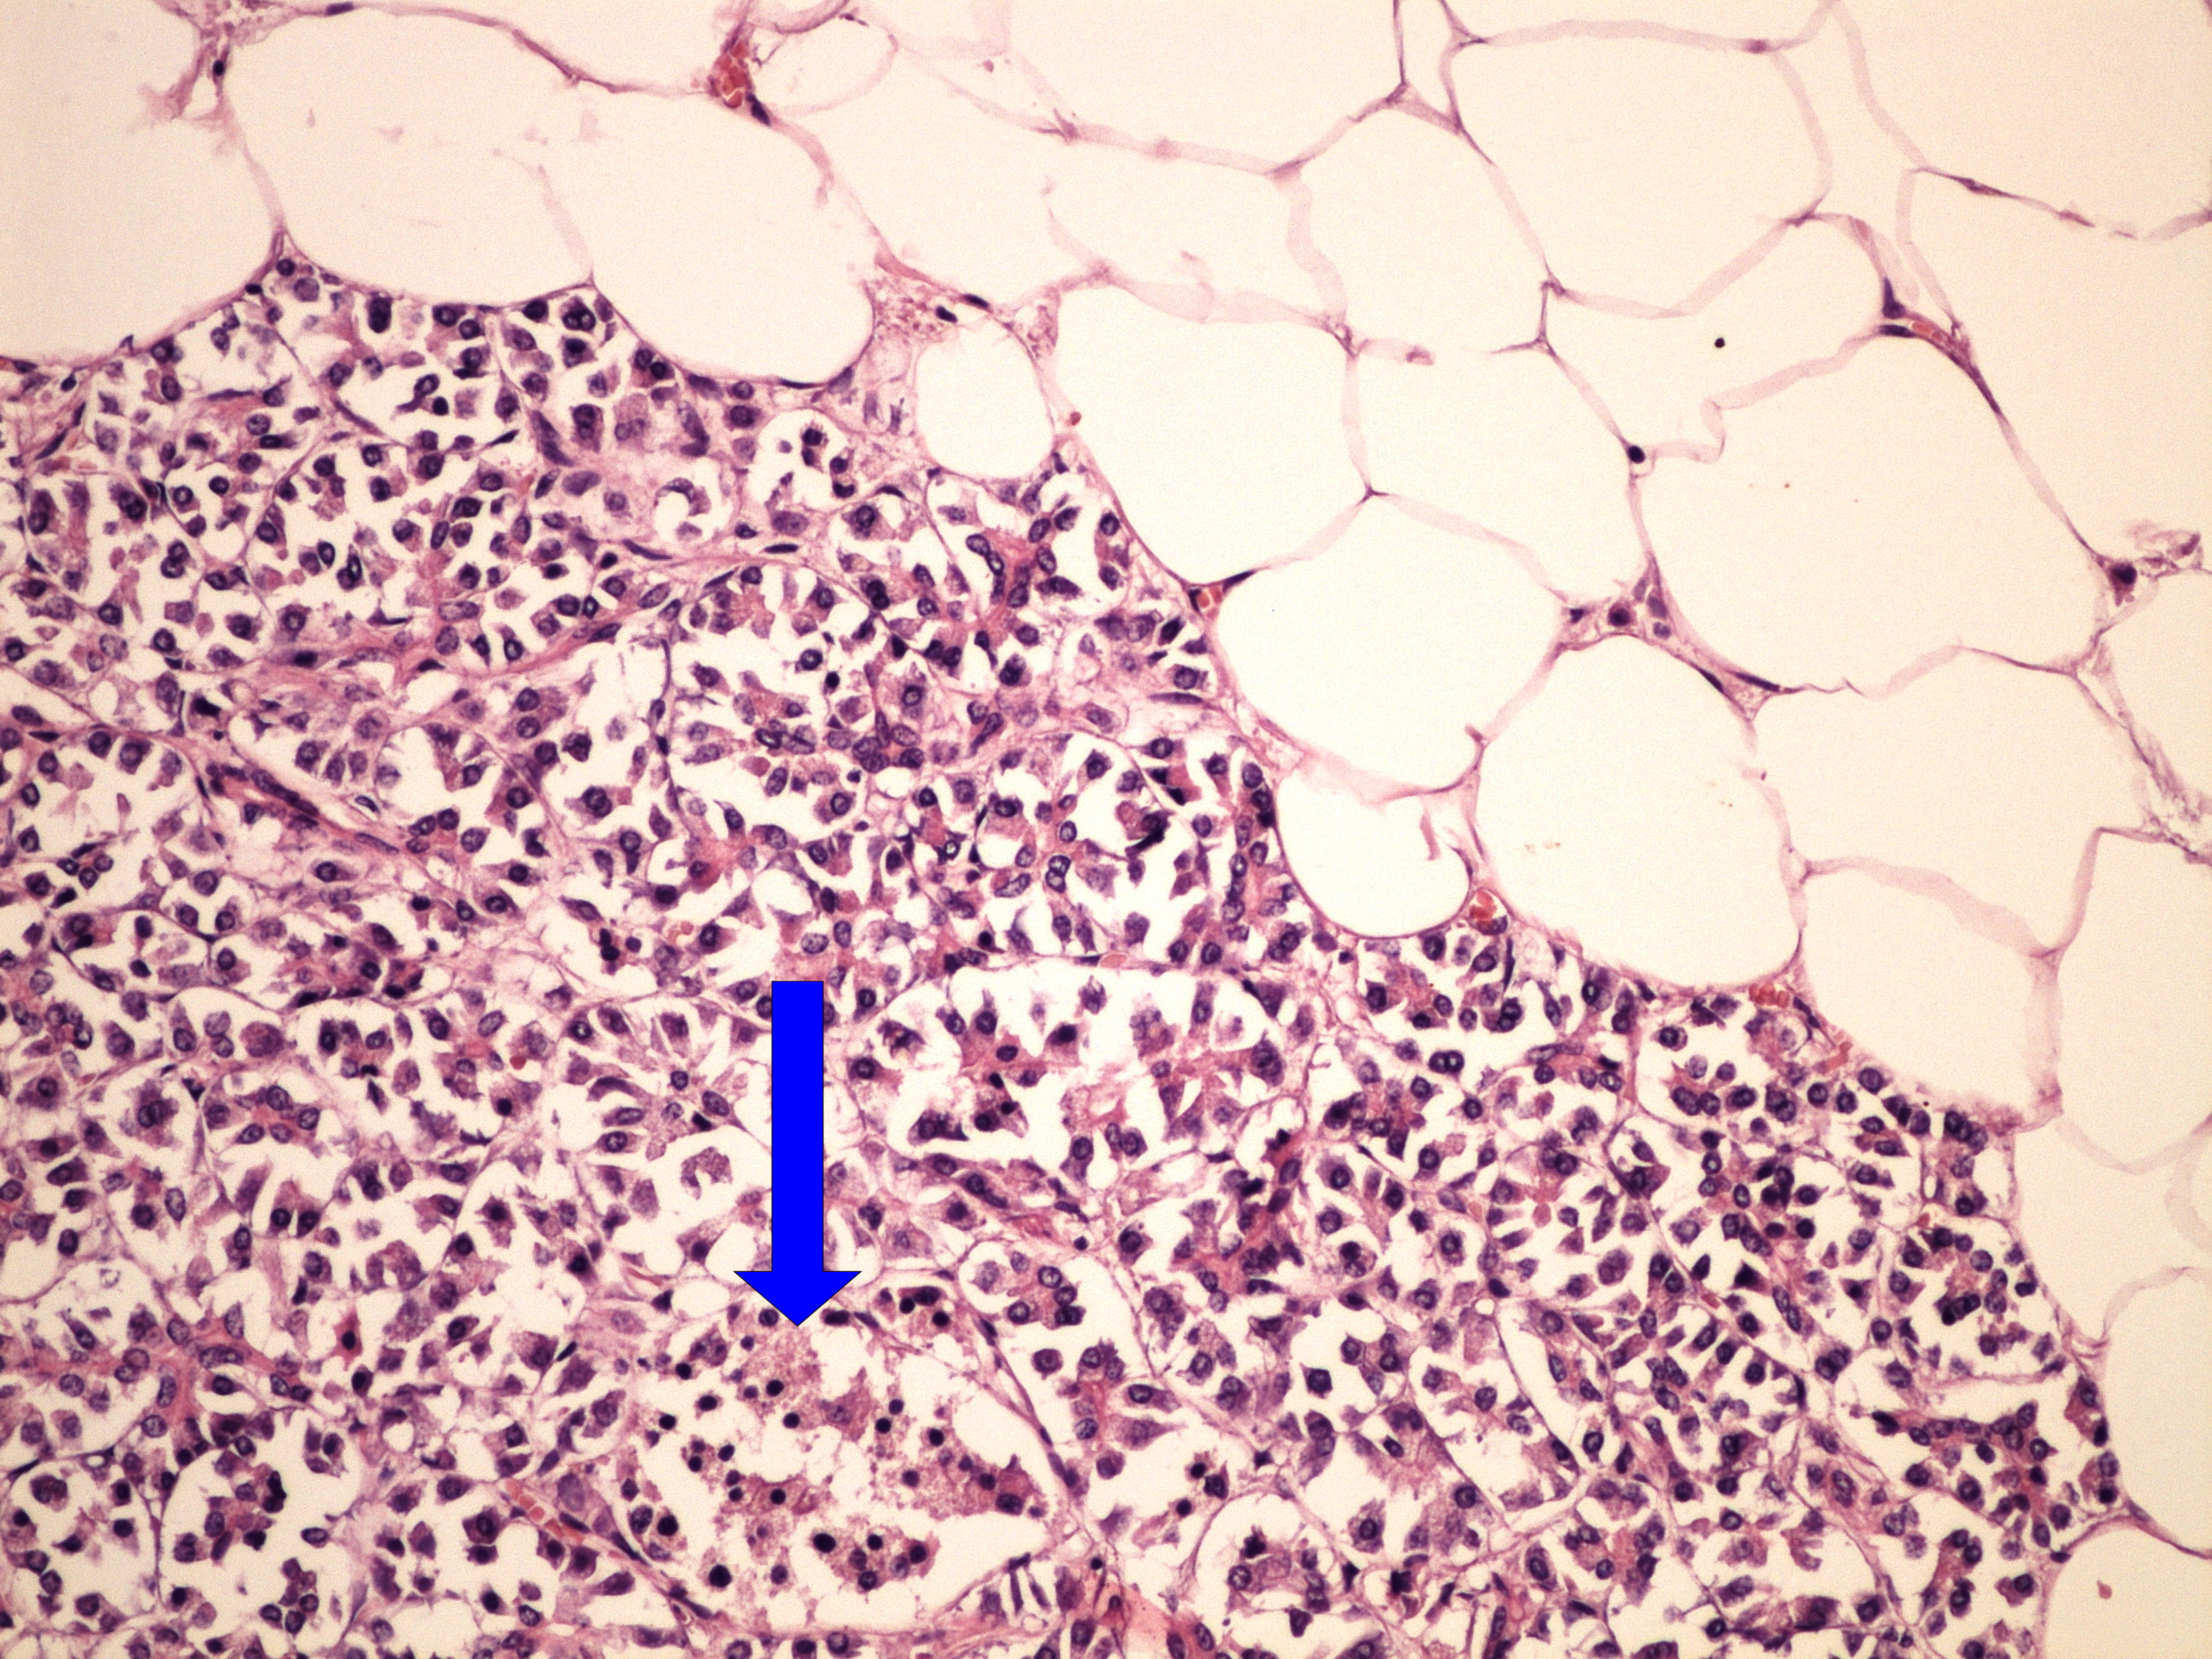

Preparát č.5 a č.6 - tuková atrofie pankreatu

Struktury

- tuková tkáň

- Langerhansův ostrůvek